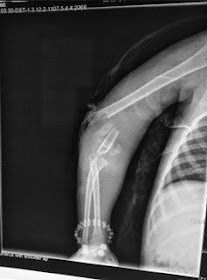

Discusión entre pares / 6 year old child having compound grade 3a fracture of distal humerus

https://www.facebook.com/groups/indian.ortho/

6 year old child having compound grade 3a fracture of distal humerus.

Neurovascular status good

Critical comments please.